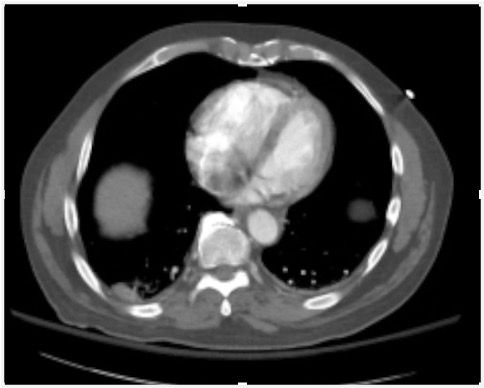

A middle-aged male presents with chest pain and shortness of breath. What is the diagnosis?